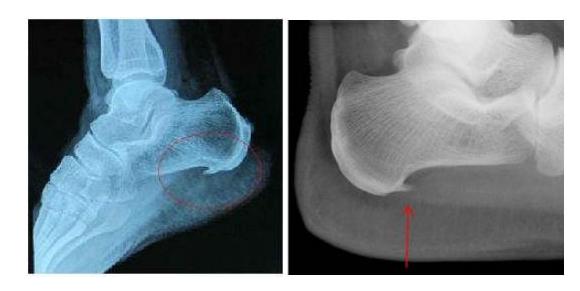

(3)跟骨

跟骨承受的重量很大,这个部位比较容易出现骨刺。不少任会出现脚后跟疼的症状。一旦出现此症状,建议去看医生。